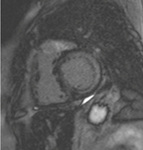

Ressonância nuclear magnética cardíaca (RNMC) de paciente com infiltração amiloide cardíaca. Após injeção de contraste de gadolínio, na fase tardia há um anel basal subendocárdico no ventrículo esquerdo (corte de 4 câmaras)

Do acervo de Dr Jessica Webb; usado com permissão